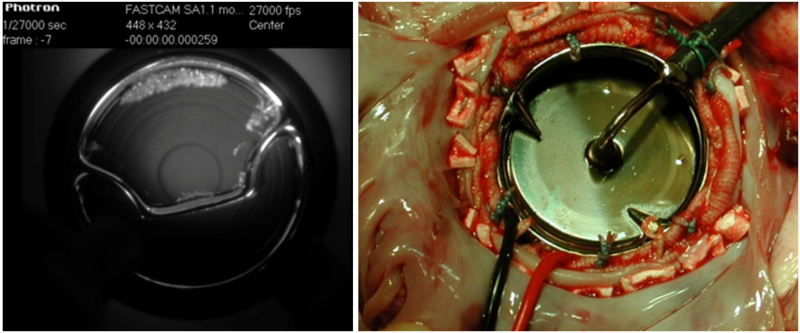

The primary focus of our investigations is on the test and evaluation of prosthetic heart valves both surgical types (mechanical and bioprosthetic) and percutaneous catheter inserted valves (TAVI), as well characterising the effect of various types of surgical procedures.

In the CAVE lab, our experimental modalities include recording of pressure (Millar microtip catheters), flow (Transonic transit time flowmeter and GE Vivid i ultrasound scanner), high speed imaging (two Photron Fastcam SA3 for 3D analyses), digital image correlation analysis for strain recording in tissues (ARAMIS software), custom built strain gauge based transducer (for force measurements in various structures) and 3D print of force transducers, flow phantoms or other structures.